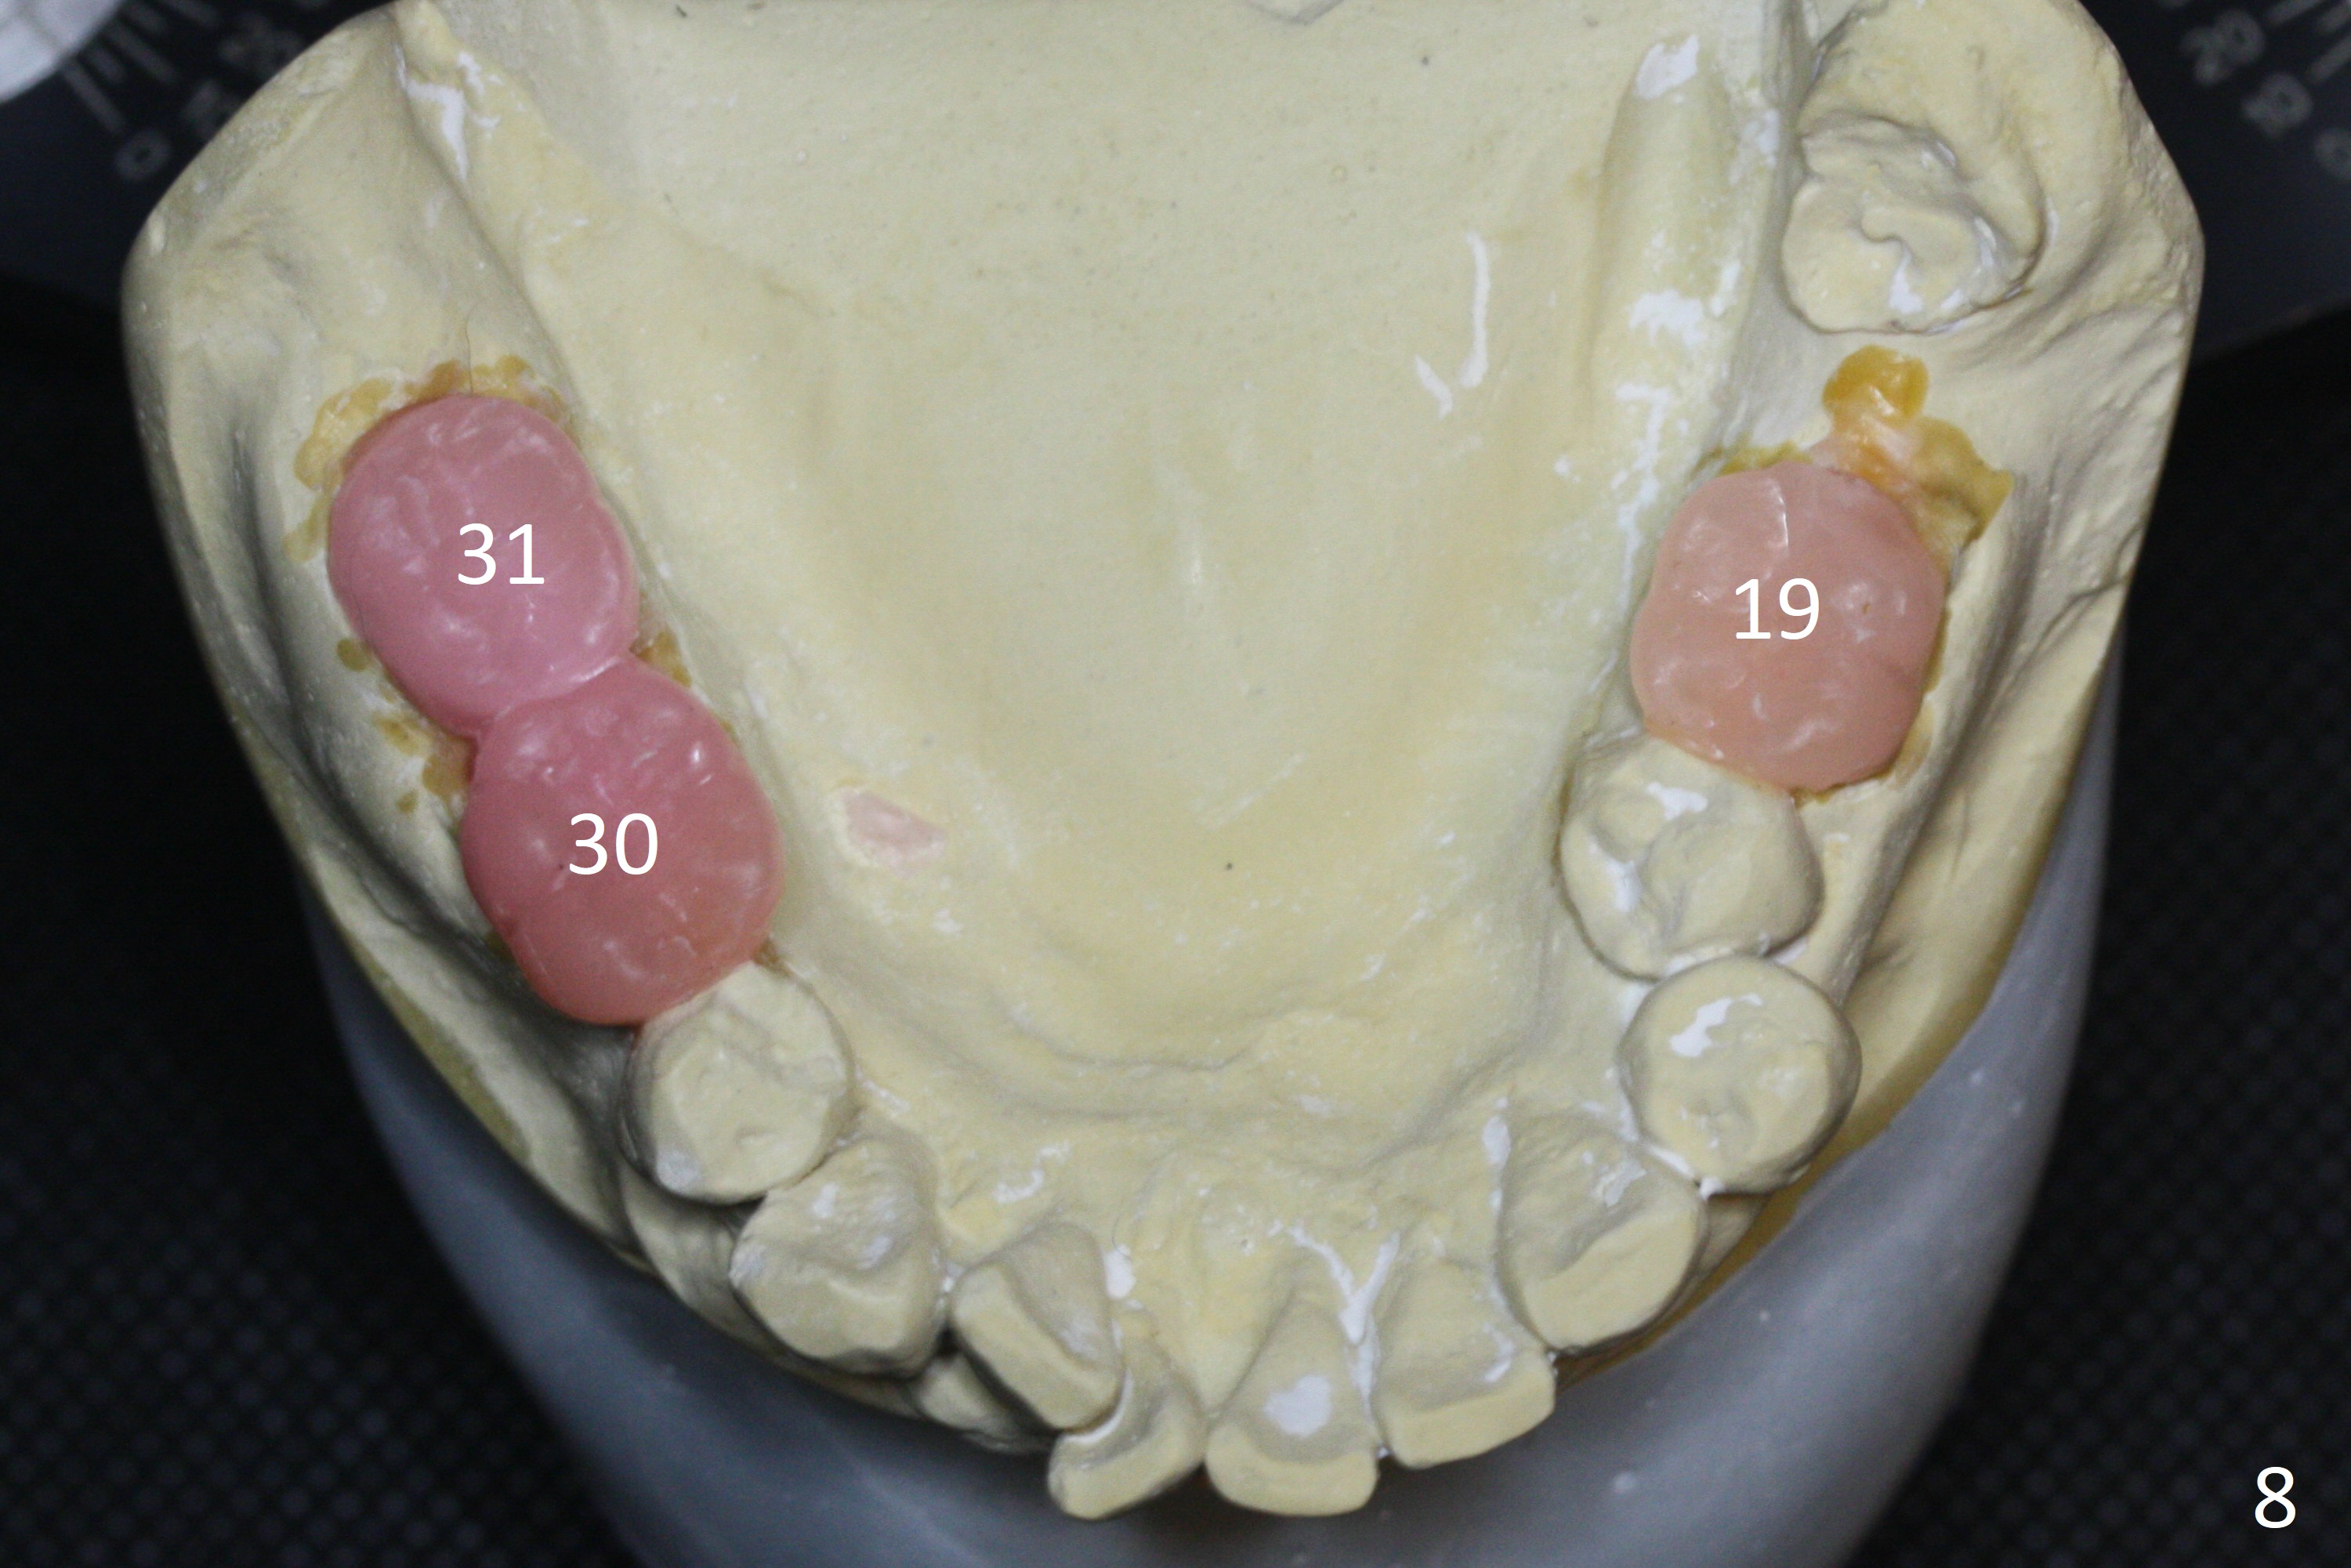

A 54-year-old man is 5 years post liver cancer surgery. After his platelet count returns normal, he wants to take care of his teeth. Most of his molars (#14, 19, 30,31) need extraction and implant placement (Fig.1-4). Although the 2nd premolars on the right are missing (Fig.1,3,4), it seems appropriate to establish 2 molar occlusion on the right (Fig.5,7,8) and 1 on the left (Fig.6,7 (because of #15 supraeruption (Fig.2 arrow))) . Since the residual roots in the lower right quadrant are irritating, implant placement will be done first (Fig.11, Clindamycin), followed by #2,3 (Fig.10) and 14(Fig.12 IBS) and 19 (Fig.12). Use IS drills and 4 and 5 mm stoppers to start osteotomy at #30 and 31, respectively.